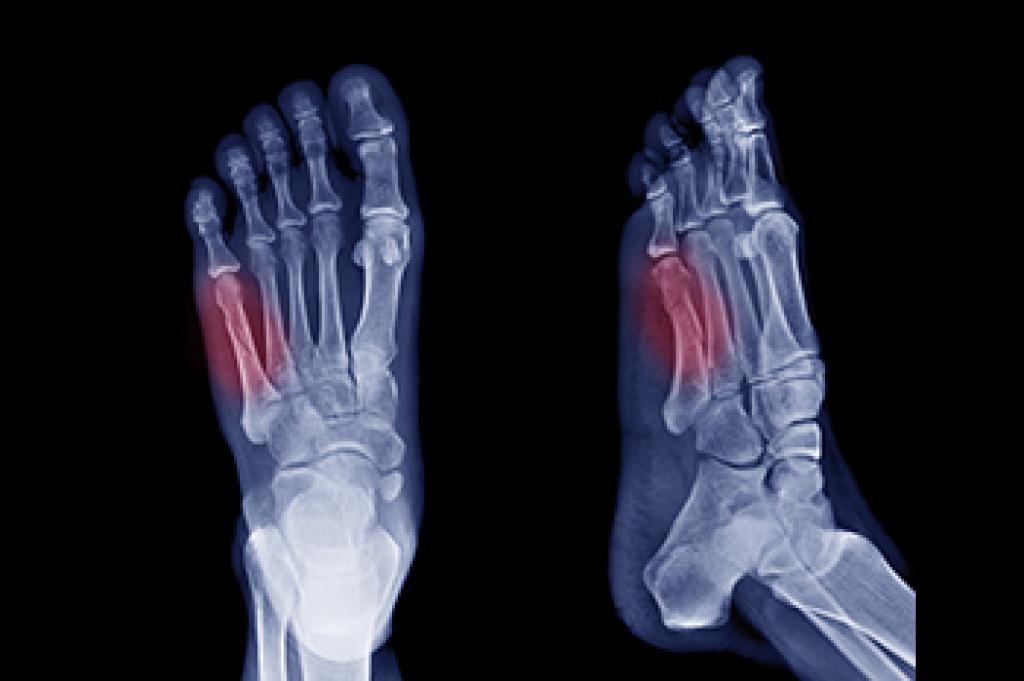

- Diagnose foot ailments such as ulcers, tumors, fractures, etc.